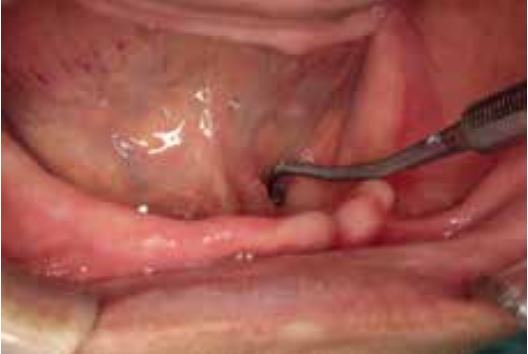

Đánh giá mô mềm trong miệng

Bốn yếu tố hoặc thông số then chốt đóng vai trò quan trọng trong việc đạt được hiệu ứng hít dính hiệu quả và do đó cần được đánh giá trước khi bắt đầu điều trị.

Mức độ phức tạp của quy trình làm hàm giả sẽ phụ thuộc vào các yếu tố này.

- Hình dạng xương ổ răng thuận lợi và có đủ mô niêm mạc trên sống hàm.

- Có nhiều mô xốp ở vùng nếp dưới lưỡi.

- Gối hậu hàm có hình dạng rõ rệt, hình quả lê.

- Có đủ khoảng không gian trong hố sau cơ hàm móng (retromylohyoid fossa), cho phép kéo dài nền hàm giả.

Đối với những trường hợp đáp ứng đủ bốn yêu cầu này, có thể chế tạo hàm giả hàm dưới với hiệu ứng hít dính hiệu quả.